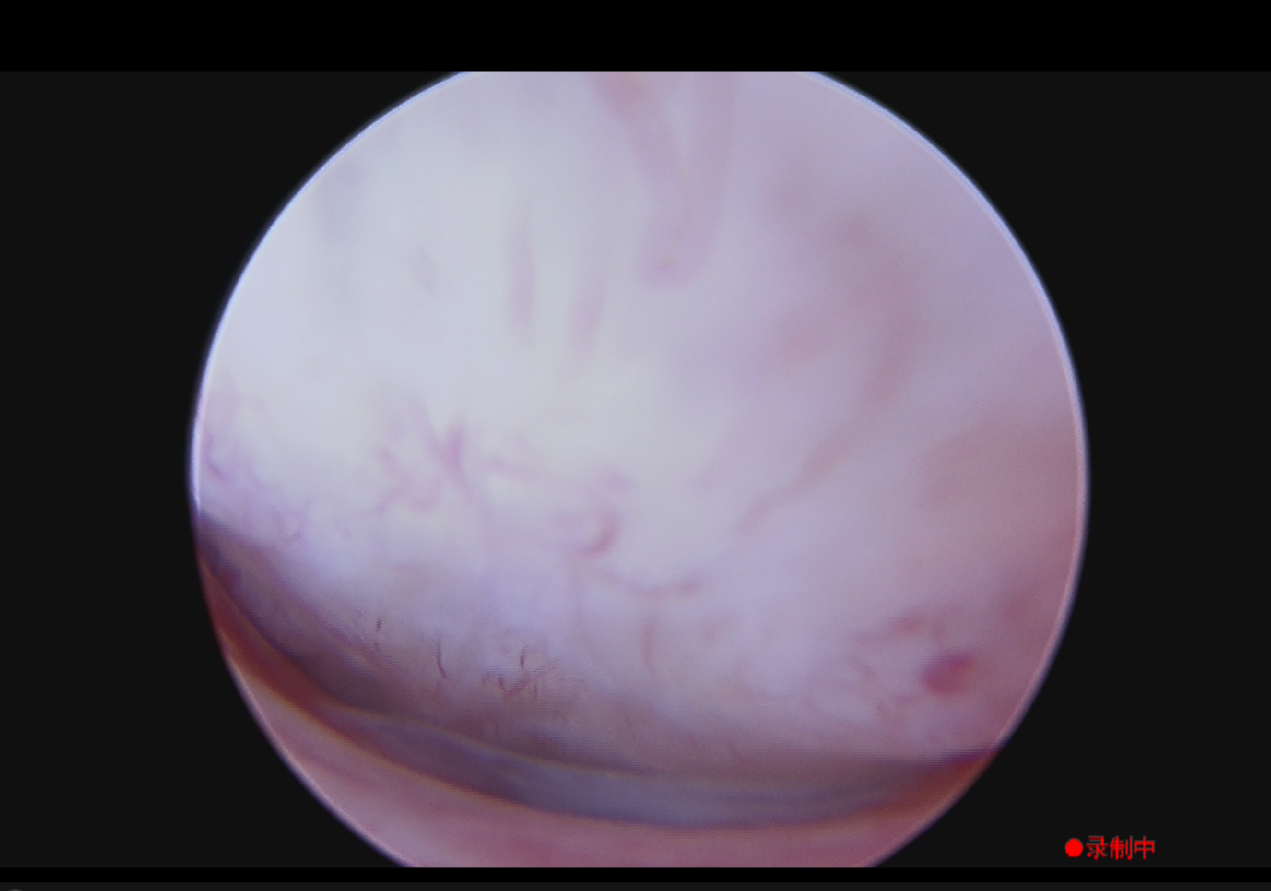

图3.术后探查宫腔内壁平整,无残留赘生物组织,未损伤周围组织